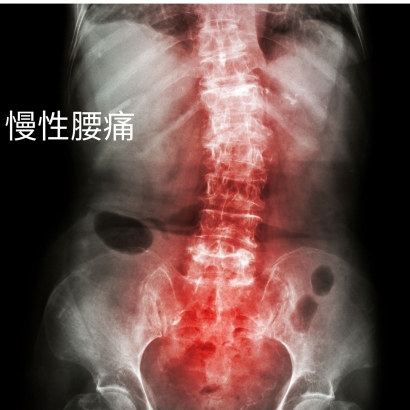

慢性腰痛的真相:為什麼疼痛總是反覆發作?

為什麼有時候搬重物沒有問題,而有時候搬相對輕的物品卻導致腰痛?即使糾正坐姿,是否問題就能完全解決呢?為什麼在躺下休息時,腰痛依然不見緩解呢?